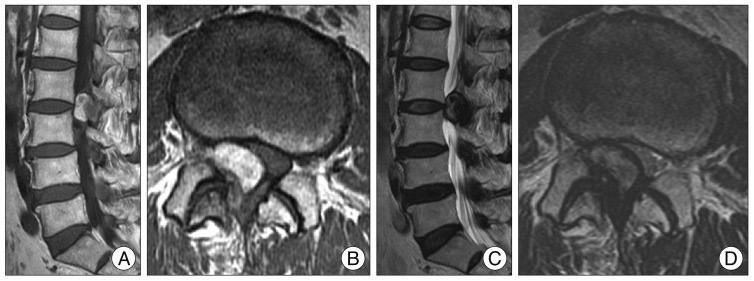

14 окт 2024

У пожилого мужчины после переохлаждения резко появилась задержка мочеиспускание, урологи утверждают, что у него – острый простатит. А на Магните – типичный рак, по крайней мере, PI-RADS 5.

Как считаете, может ли острый простатит выглядеть вот так? Асимметричный, с достаточно чётким контуром, да ещё и с быстрым накоплением контраста и быстрым же его вымыванием?

Что-то я сильно сомневаюсь, поделитесь опытом.